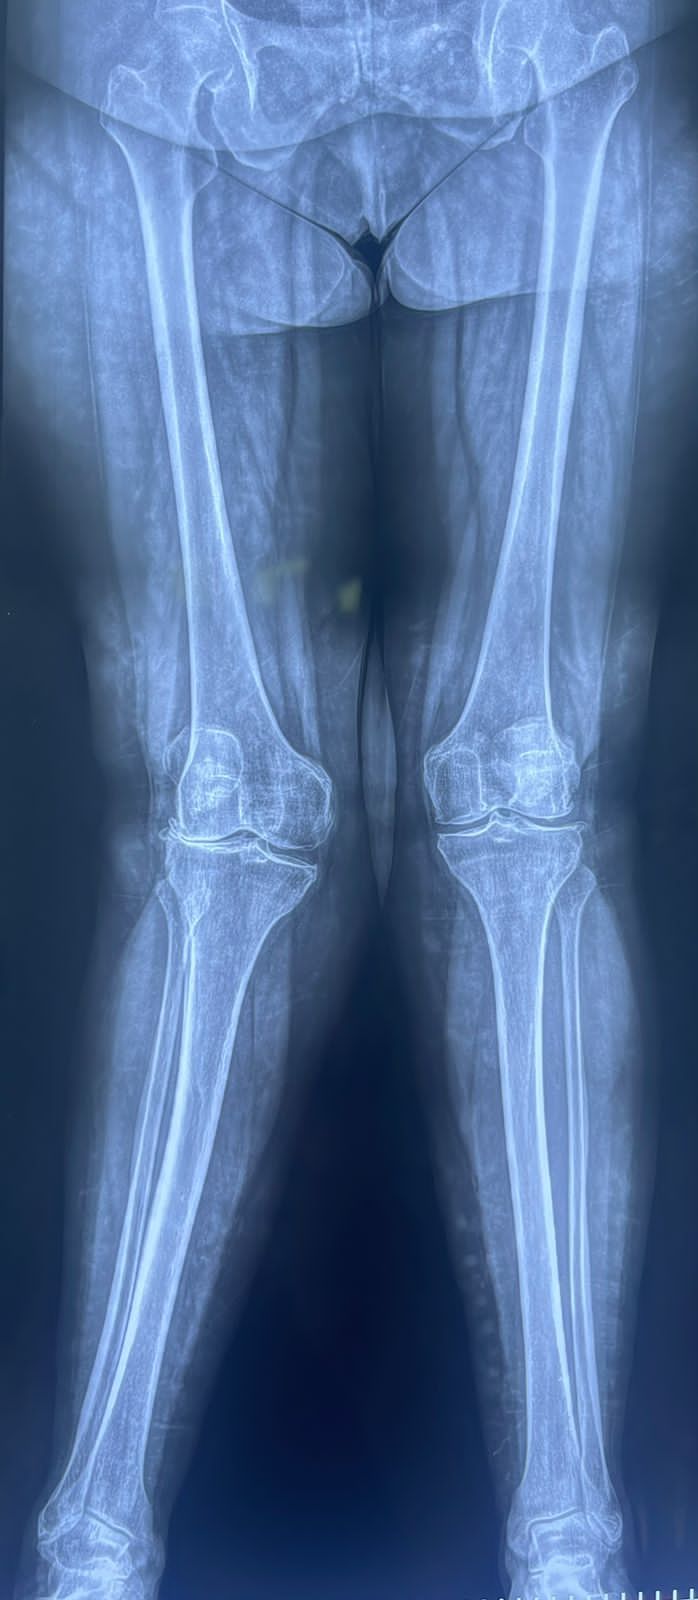

Fotos y videos